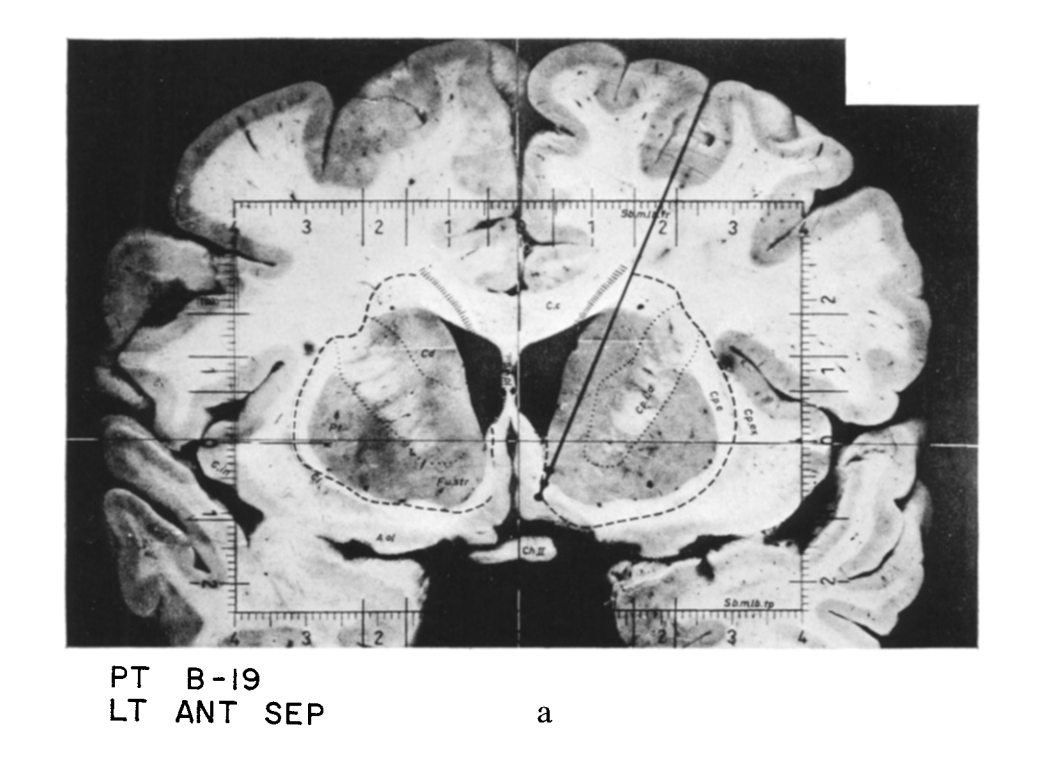

VTA âĄïž NAc).Robert Heath

During these sessions, B-19 stimulated himself to a point that, both behaviorally and introspectively, he was experiencing an almost overwhelming euphoria and elation and had to be disconnected, despite his vigorous protests.